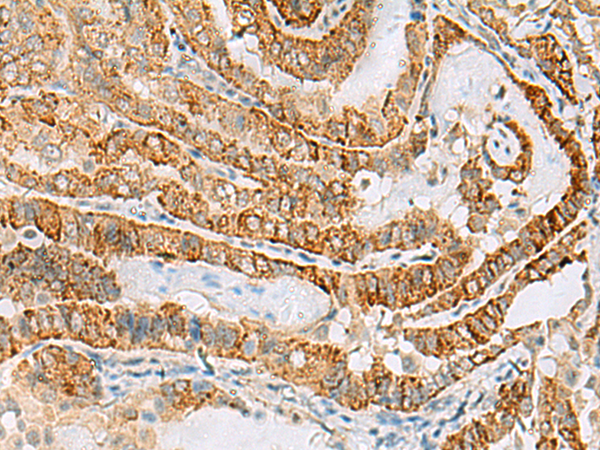

分类: 科研抗体货号: P10208别名: BG; MPS7应用: WB,IHC反应种属: Human